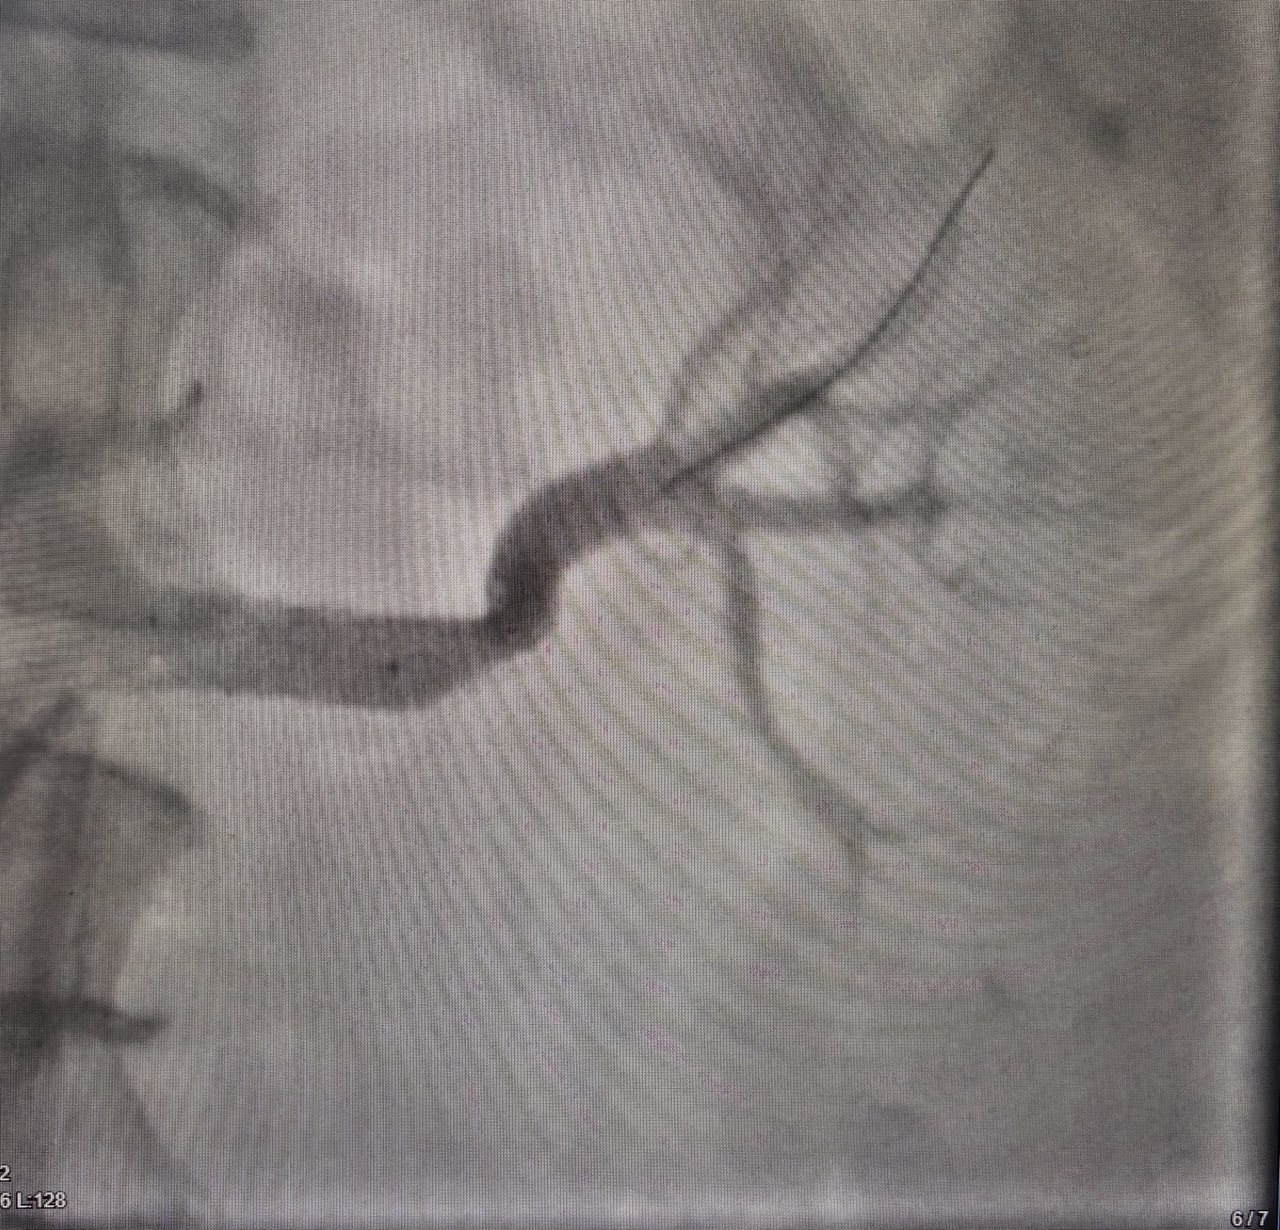

Врачи провели КТангиографию брюшной полости. Этот точный метод позволил детально изучить сосудистую систему и оценить состояние артерий в реальном времени.

Результаты исследования выявили критическую патологию — стеноз (сужение) левой почечной артерии до 80 %. Такая патология встречается редко — на нее приходится до 5 % всех случаев гипертонии.